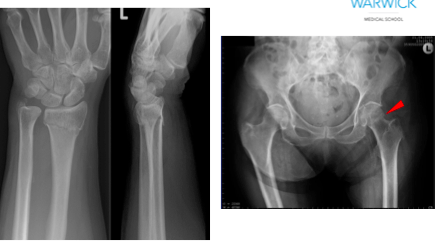

Bones most commonly fractured = neck of femur, vertebra and wrist

What is the pathology shown?